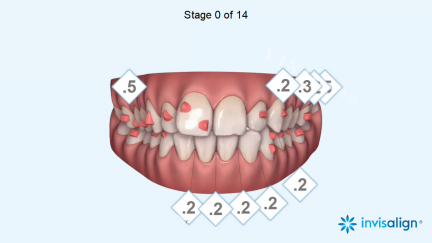

时代天使矫正:1.58万元。这是国产出名的隐形矫真正产品牌,具有美观、舒适、可摘戴等优点。

隐适美隐形矫正:3.5万元 - 5万元。隐适美是国内外出名的隐形矫真正产品牌,其矫正方案更加更准一些,佩戴舒适度更高。